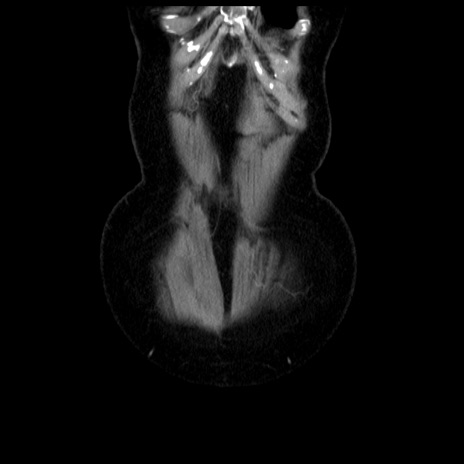

横断像

【症例】70歳代女性

【主訴】腹痛、嘔吐

【現病歴】15時間程前(昨晩)より腹痛あり。今朝になっても症状の改善なく、嘔吐あり。腹痛も増悪あり、救急外来受診。

【既往歴】子宮癌全摘術後

【身体所見】意識清明、BP 121/72mmHg、P 74bpm、SpO2 100%(RA)、腹部:平坦・軟、腸雑音ほぼ聴取せず。下腹部・心窩部・臍左上に圧痛あり。反跳痛なし。

【データ】WBC 10600、CRP 0.15